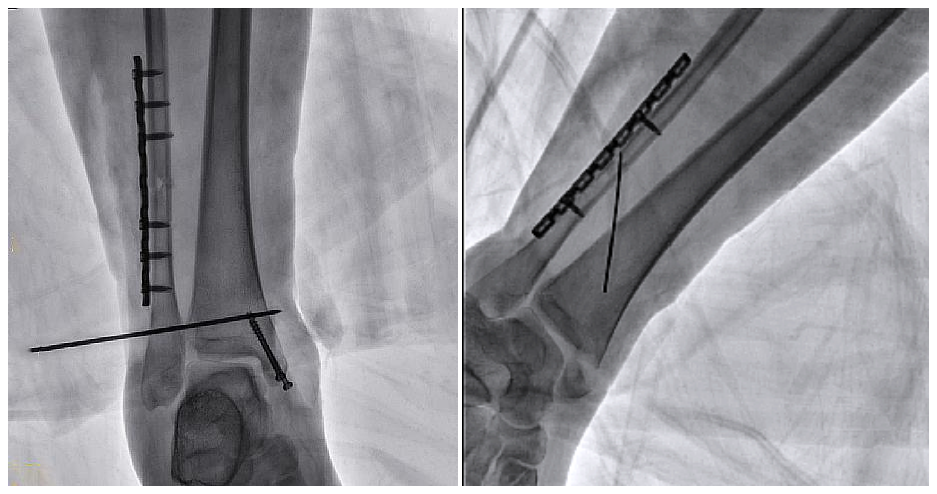

病例2 踝關(guān)節(jié)骨折復(fù)位(31歲)

在踝關(guān)節(jié)骨折復(fù)位手術(shù)中,用三維C可以更好地觀察骨折部位的復(fù)位情況:

正側(cè)位影像觀察脛腓聯(lián)合復(fù)位良好

從三維影像看,復(fù)位欠佳,貼合度不夠

二維C形臂提供的影像存在固有局限性,其成像原理是基于單一方位的投影,導(dǎo)致深部解剖結(jié)構(gòu)信息缺失,且容易受到骨骼和組織的重疊干擾,使得部分病灶難以清晰顯示,甚至被掩蓋。相比之下,三維C形臂通過三維重建技術(shù),可以獲得類似CT的斷層掃描圖像,從而解決了二維影像的重疊問題。

醫(yī)生能夠利用這些三維圖像,更直觀、更深入地分析病變,進(jìn)行全方位觀察,例如:精確評估骨折復(fù)位情況、清晰顯示內(nèi)植入物的位置及其與周圍組織的關(guān)系等。尤其在復(fù)雜骨折、脊柱手術(shù)、呼吸介入等臨床場景中,三維C形臂提供的詳細(xì)信息對手術(shù)導(dǎo)航和療效評估至關(guān)重要。